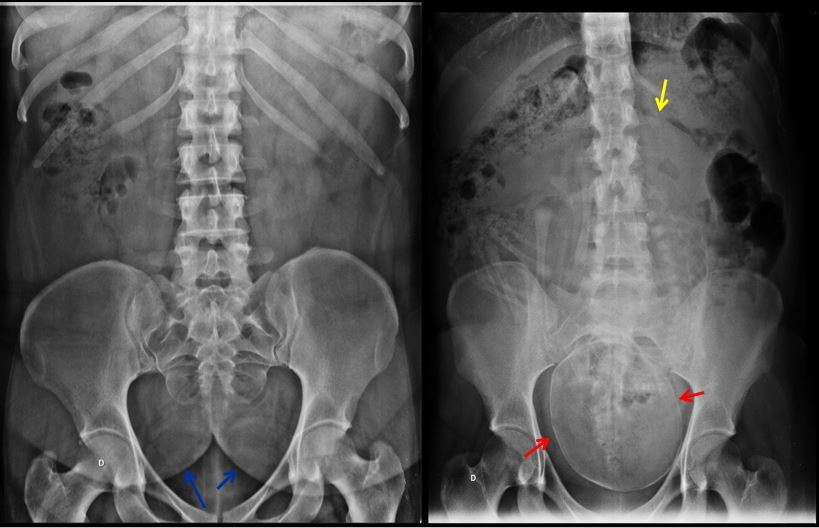

Q

IDENTIFIQUE AS SETAS E DIGA PQ SÃO ADULTOS

SETAS AZUIS – NÁDEGAS DE UMA SENHORA OBESA

SETAS VERMELHAS – POLO CEFÁLICO DE UM FETO.

SETA AMARELA – CONTORNO UTERINO . OBSERVE O DESLOCAMENTO DAS IMAGENS GASOSAS COLÔNICAS.

SÃO ADULTOS PORQUE JÁ OCORREU A FUSÃO DAS LINHAS DE CRESCIMENTO.